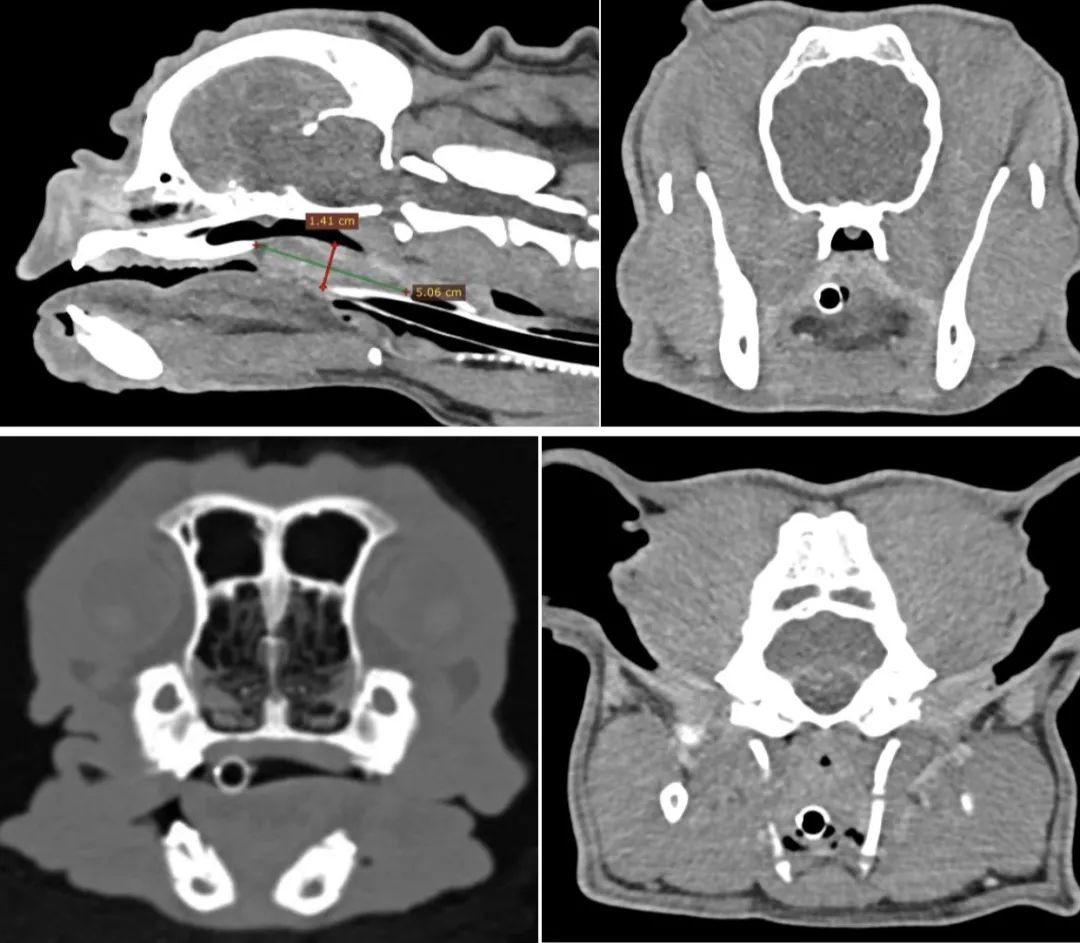

4.转诊中心医院CT 检查

法斗呼吸不畅、运动不耐受,通过CT扫查发现鼻咽部息肉、软颚肥厚↓↓

未成年小猫出现流口水与呆滞表现,在家观察后症状严重,双目失明,后肢无力,隔天出现抽搐的表现,来院检查后CT诊断,发现小猫出现了罕见的pss(先天性肝脏门静脉短路),血氨已经超正常值十倍,在两天的对症治疗后现在体征恢复平稳,择日手术治疗↓↓

宠爱国际是国内较早使用SIEMENS ESSENZA 1.5T 超导核磁共振及SIEMENS 64排螺旋CT等影像设备的宠物医疗机构。高阶影像诊断中心MRI为高磁场(1.5Tesla)新机型,与一般低磁场或旧机型相比较,大幅降低检查时间。其高度解析能力,对动物脊椎神经和肿瘤能提供极佳诊断依据。高阶影像诊断中心CT为64切电脑断层摄影(CT),可在数十秒内完成动物大区域的空间扫描,比一般标准X光机更加详细,几乎全身各个部位都能快速检查与筛检。宠爱国际高阶影像诊断中心影像团队判读经验丰富,在2018年建立影像诊断&肿瘤治疗中心后开始就不断积累影像病例,由国内影像判读专家坐镇,对超声、MRI、CT等高阶影像学的判读有8年多经验;还同步拥有日本、美国等国际影像判读合作,出具报告。本院全程使用教学医院麻醉方式,并配合人用等级设备,每一次的扫描过程配备麻醉专科兽医师全程监控麻醉状况,尤其在麻醉诱导与苏醒过程中全程监控,即实记录下麻醉过程中生理数据及药剂处置,以提高麻醉安全性并降低麻醉风险。宠爱国际影像科凭靠专业设备和丰富的操作与判读经验提供专业医学影像诊断、医学影像专家门诊和远程影像会诊服务,搭建医学影像诊断学术研究和交流平台;提供全面医学影像诊断解决方案,不断开展国内兽医影像学领域新项目及新课题。